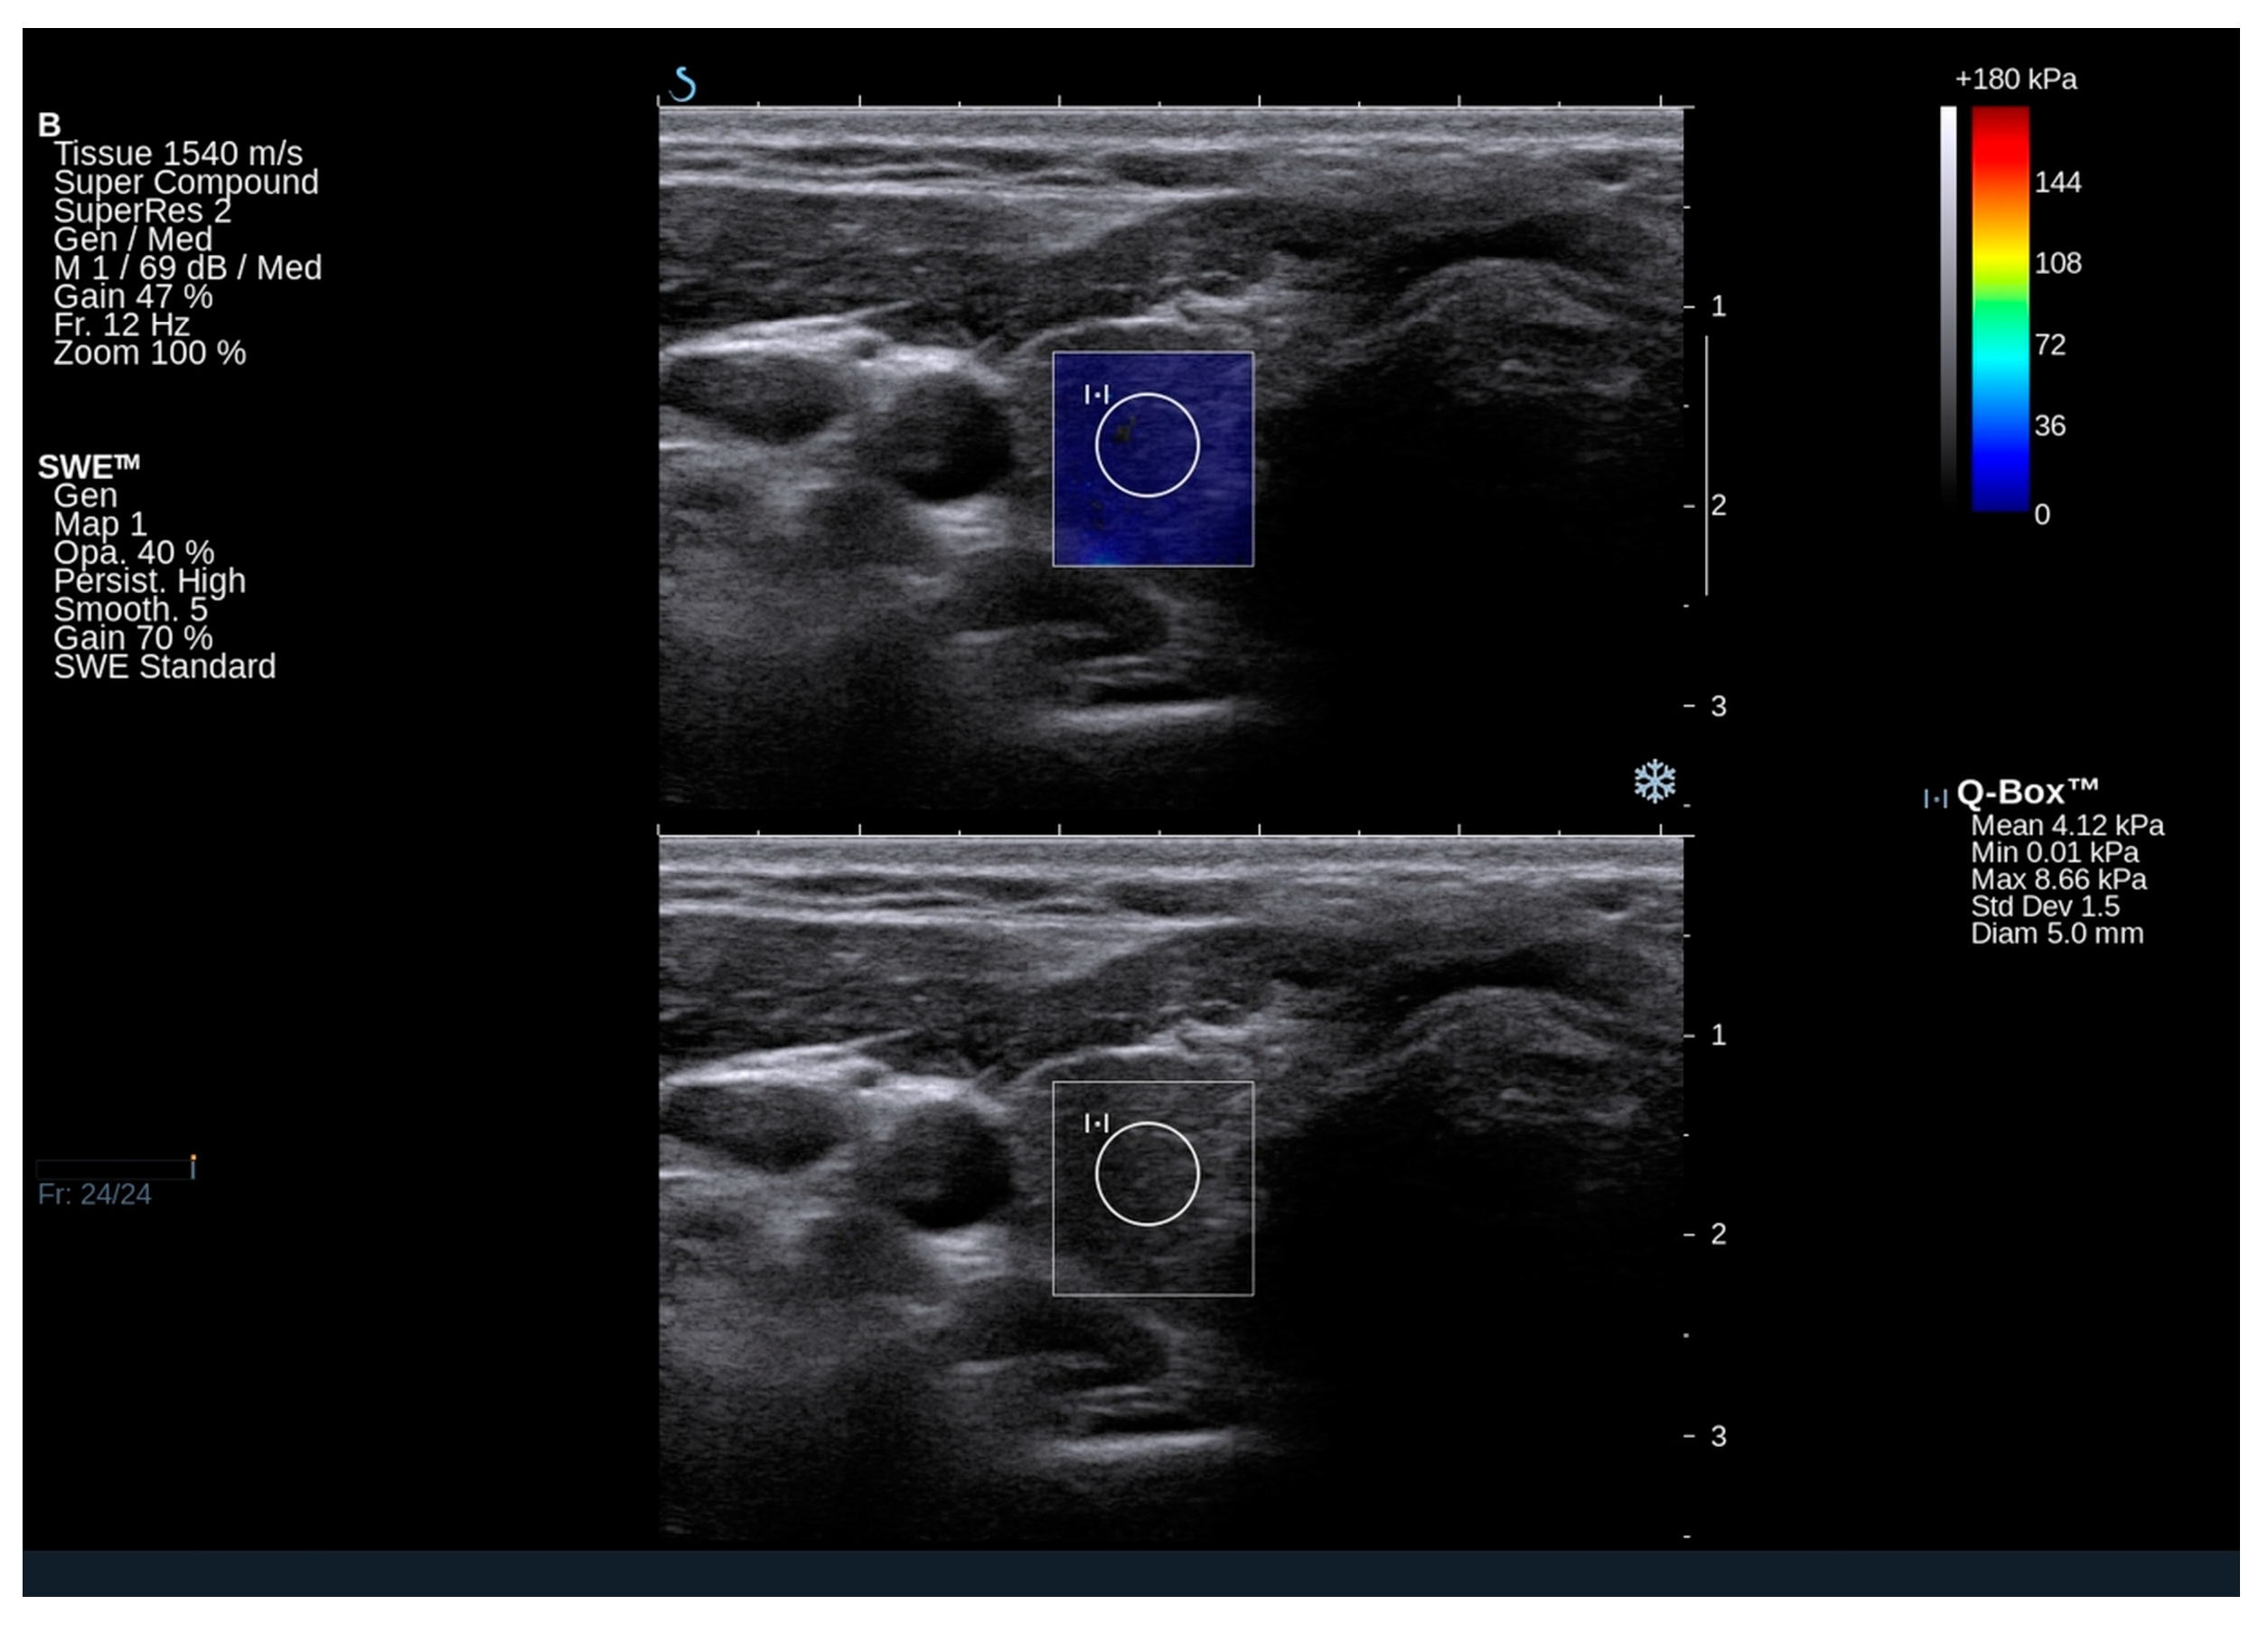

2.3. Elastography Results

4.2. Thyroid Ultrasound and Shear Wave Elastography (SWE)

| Right lobe Qbox mean (kPa) | 17.2 (11.9–20.9) | |

| Right lobe Qbox min (kPa) | 11.3 (6.8–13.3) | |

| Right lobe Qbox max (kPa) | 25.4 (18.8–31.5) | |

| Right SD | 3.5 (2.7–4.5) | |

| Left lobe Qbox mean (kPa) | 14.9 (11.3–21.5) | |

| Left lobe Qbox min (kPa) | 8.7 (5.3–12.5) | |

| Left lobe Qbox max (kPa) | 22.9 (17.3–29.6) | |

| Left SD | 3.2 (2.1–4.0) | |